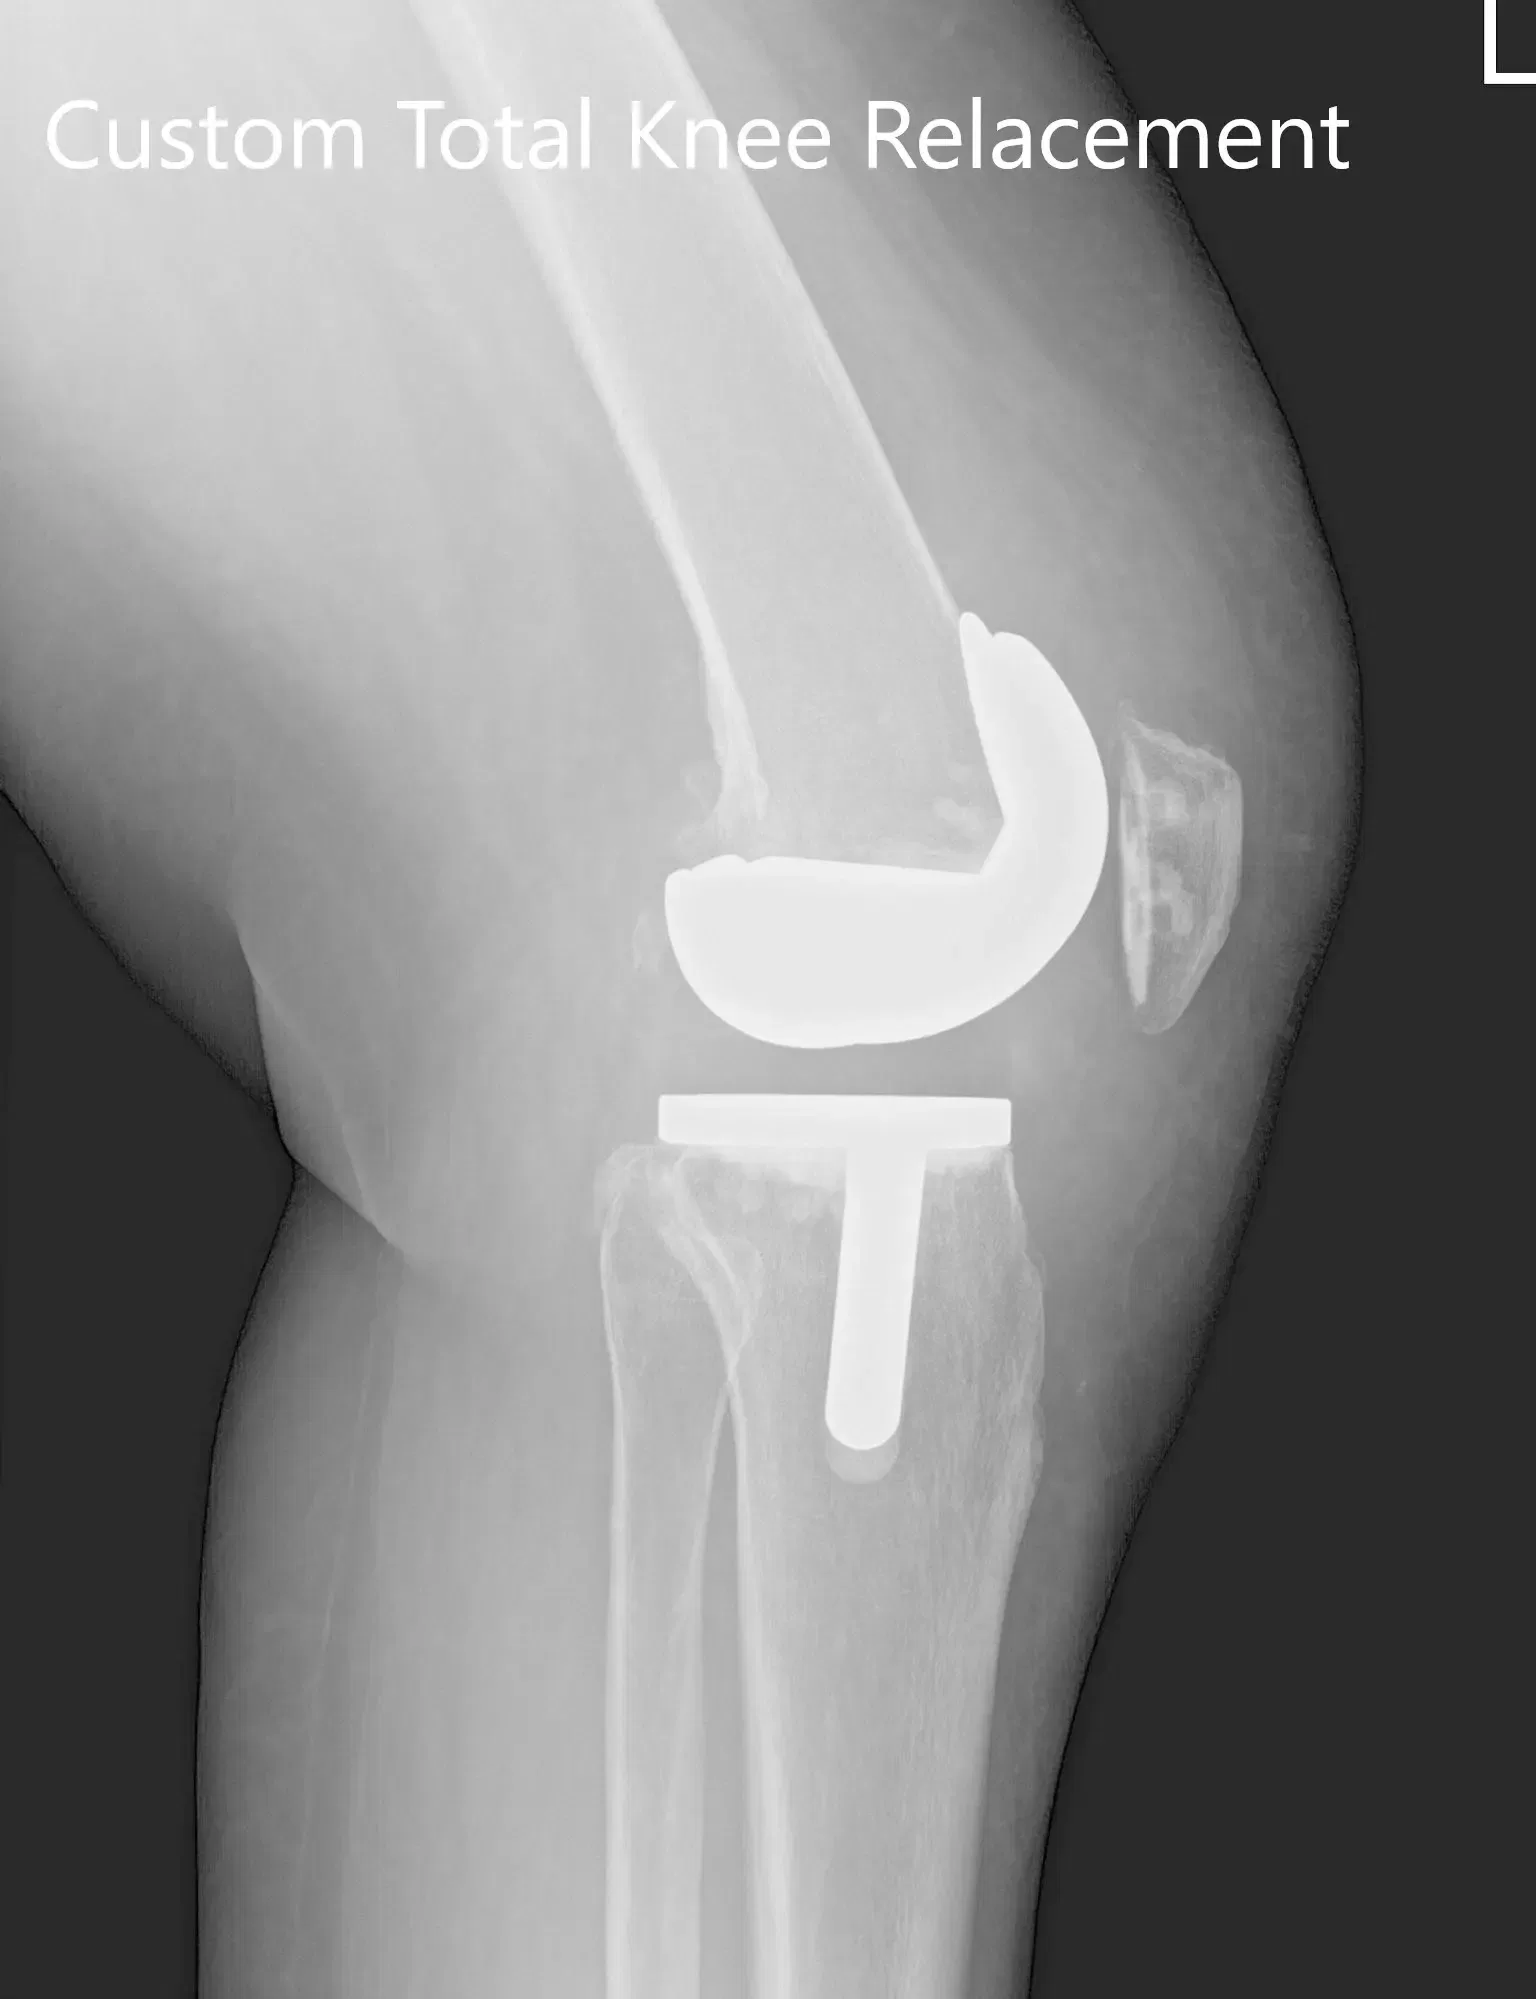

Varias semanas antes de la cirugía, se realizó una tomografía computarizada de la rodilla izquierda. Se obtuvo una reconstrucción 3D única a partir de los datos. Estos datos se utilizaron para crear un implante único y específico para cada paciente. Además, se construyeron instrumentos desechables personalizados y únicos para la rodilla del paciente. Los implantes y los instrumentos personalizados aseguraron el mejor resultado del procedimiento. Se elaboró un plan preoperatorio específico para la rodilla del paciente para preplanificar los cortes y desplazamientos óseos.

Plan quirúrgico completo de Orthopedics específico para pacientes para un reemplazo personalizado de rodilla izquierda en un hombre de 40 años.

Plan quirúrgico preoperatorio que detalla los cortes y desplazamientos óseos

El paciente se sometió a una artroplastia personalizada de la rodilla izquierda

Implante utilizado: Fémur personalizado con tibia y rótula personalizadas (38 mm x 8,5 mm) con inserto de polietileno de 10 mm.